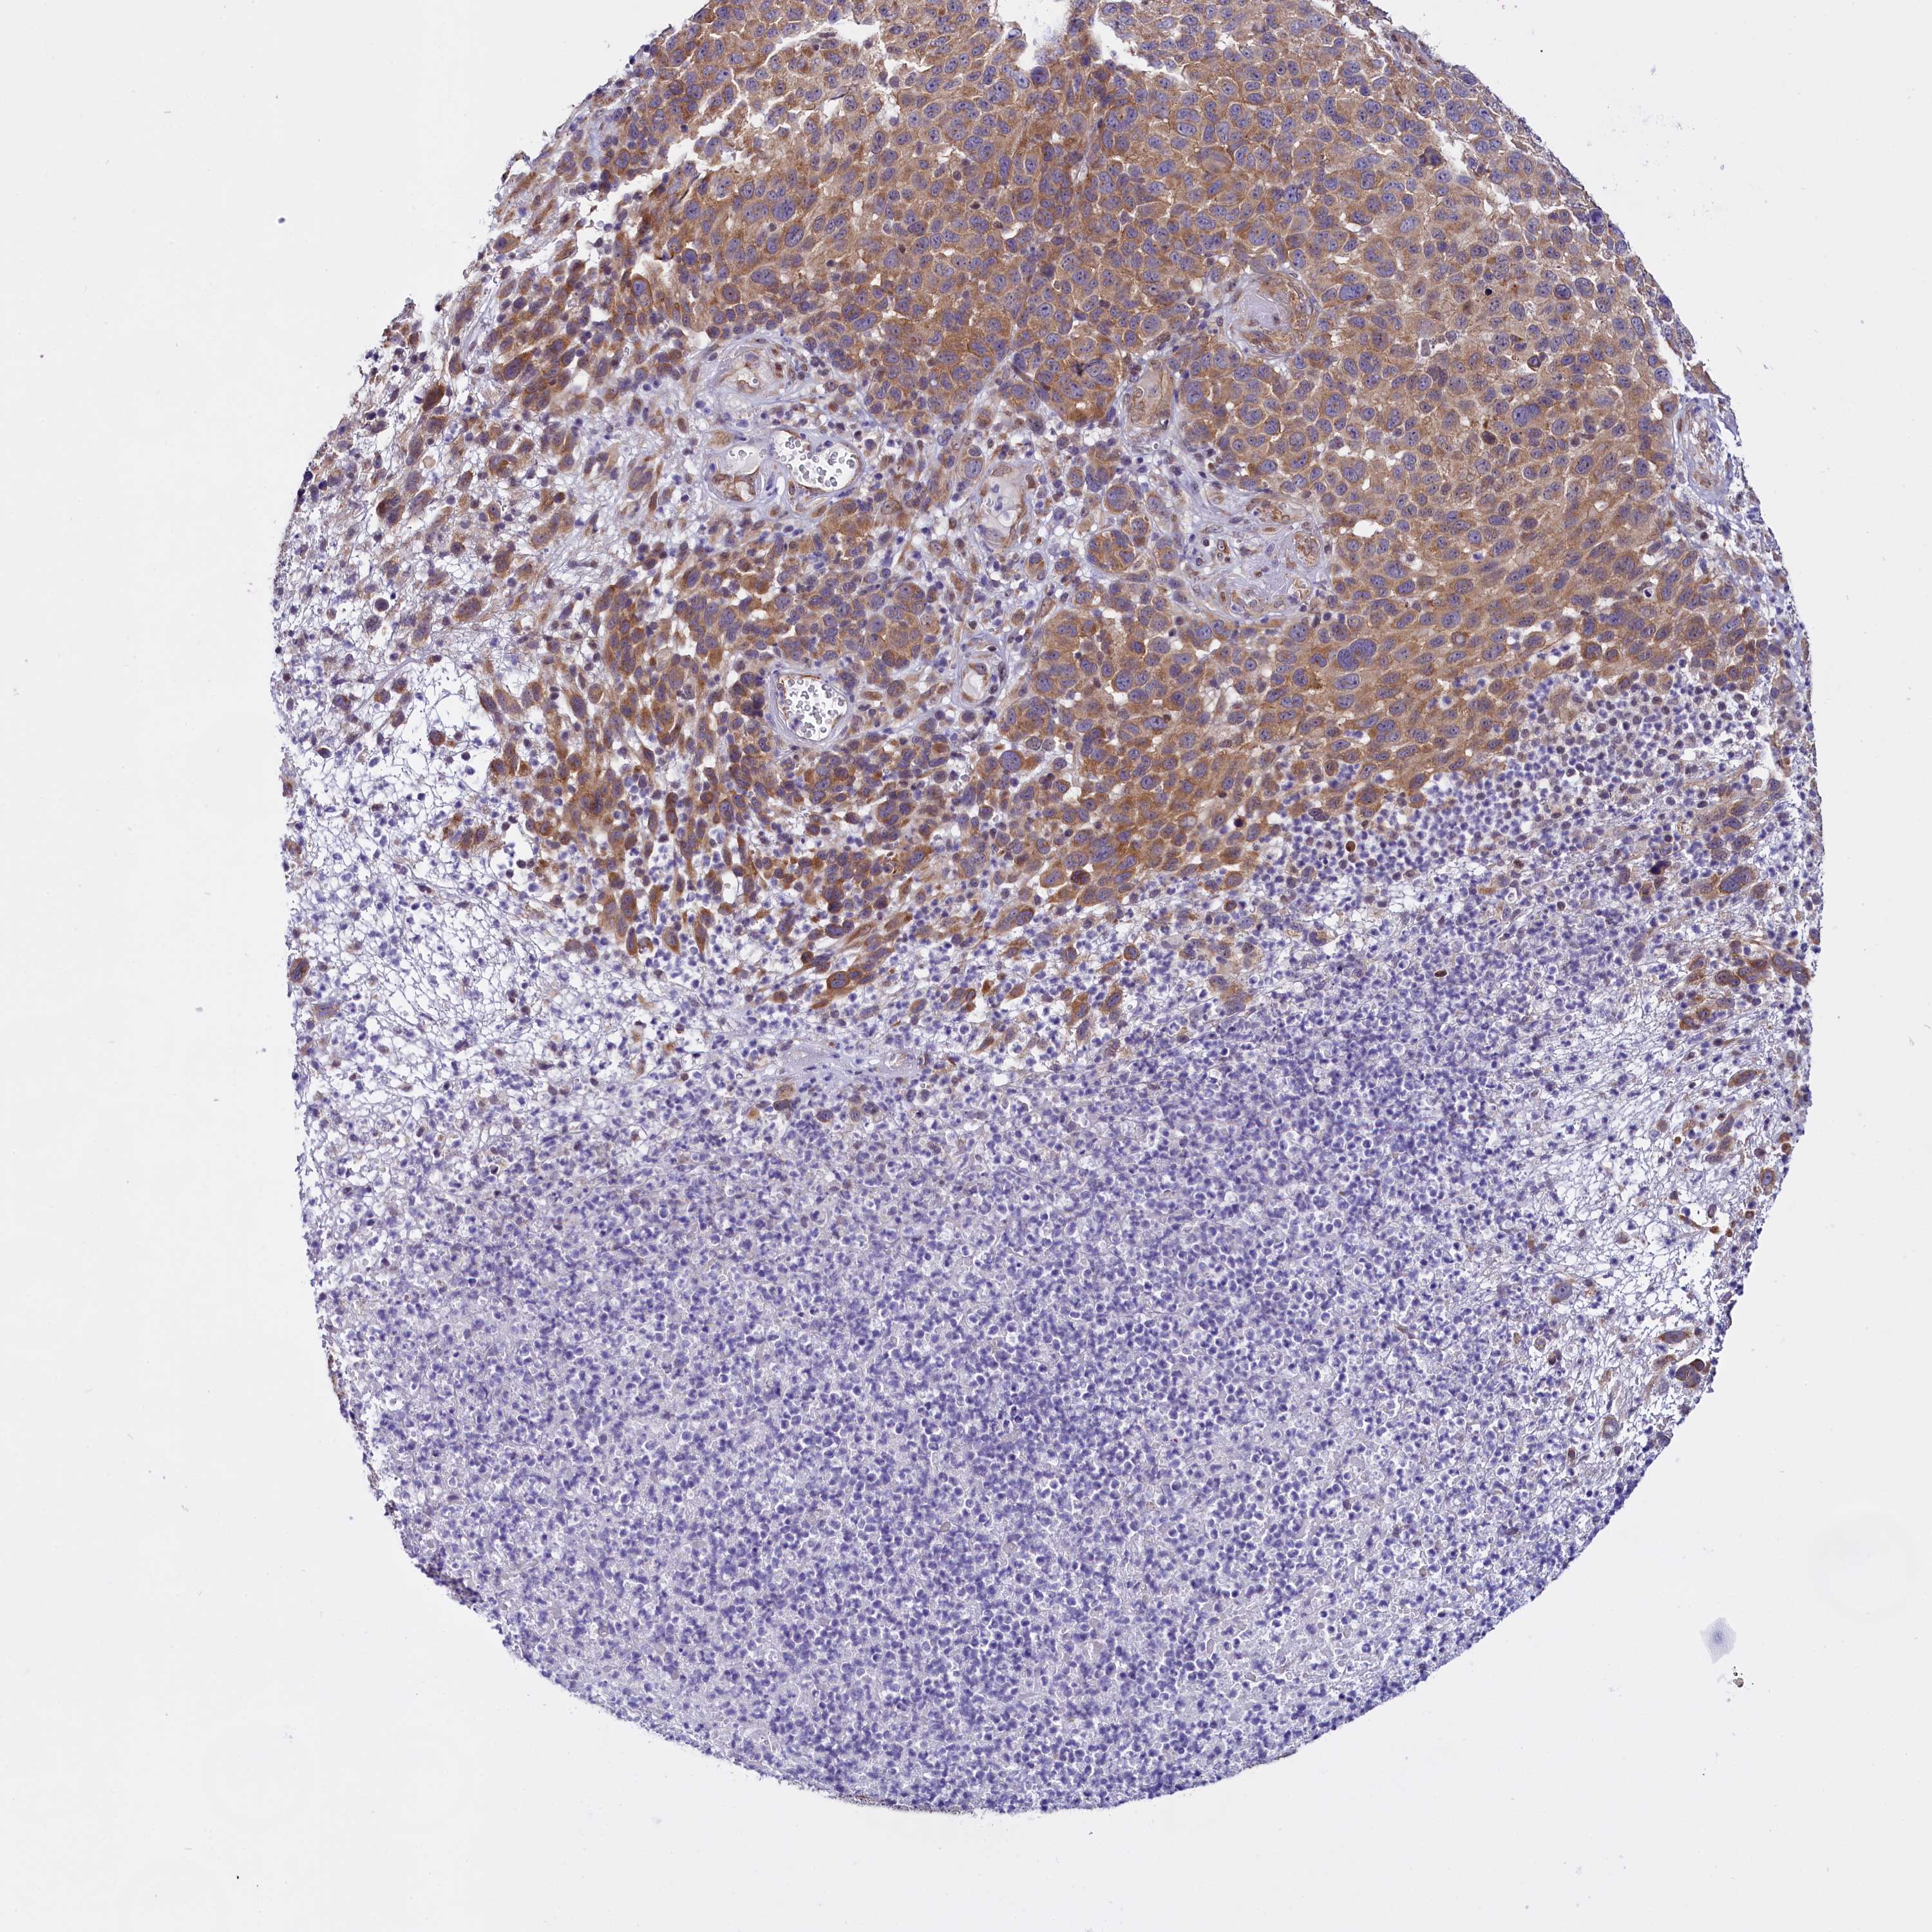

MELANOMA - Protein expressioni

A mouse-over function shows sample information and annotation data. Click on an image to view it in a full screen mode. Samples can be filtered based on level of antibody staining by selecting one or several of the following categories: high, medium, low and not detected. The assay and annotation is described here.

Note that samples used for immunohistochemistry by the Human Protein Atlas do not correspond to samples in the TCGA dataset.

Antibody stainingi

Antibody staining in the annotated cell types in the current human tissue is reported as not detected, low, medium, or high, based on conventional immunohistochemistry profiling in selected tissues. This score is based on the combination of the staining intensity and fraction of stained cells.

Each image is clickable and will lead to virtual microscopy that enables deeper exploration of all samples and also displays staining intensity scores, fraction scores and subcellular localization as well as patient and tissue information for each sample.

Antibody HPA041412

Antibody HPA056006

Staining

High

Medium

Low

Not detected

Intensity

Strong

Moderate

Weak

Negative

Quantity

>75%

75%-25%

<25%

None

Location

Nuclear

Cytoplasmic/membranous

Cytoplasmic/membranous,nuclear

Malignant melanoma, NOS

Malignant melanoma, Metastatic site